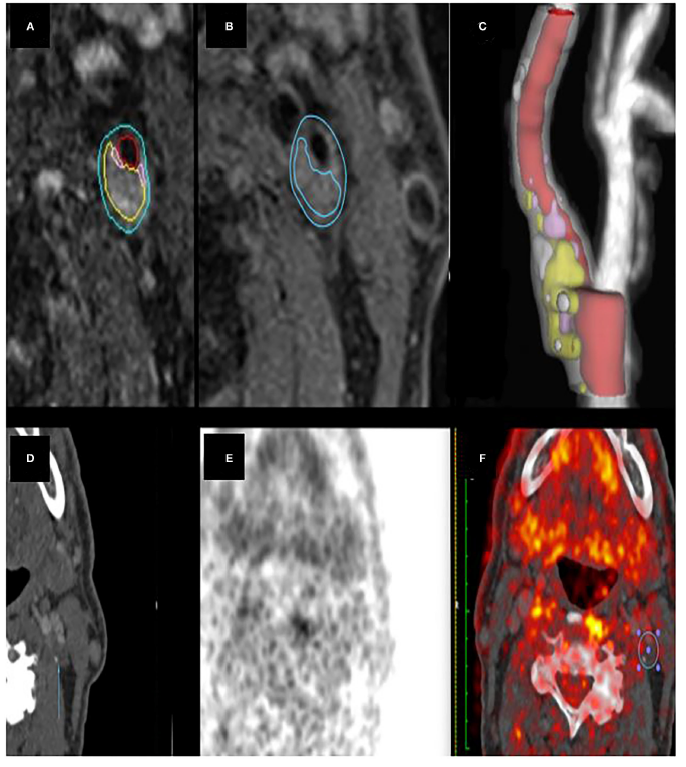

(A) 颈动脉 MRI 管腔和血管壁半自动分割。(B)半自动分析的 LRNC区域 。(C) 颈内动脉的3D 渲染。(D-F) 同一斑块区域的 CT 和 PET 图像。ROI (F) 显示了测量 SUVmax 的位置。

0.03)较大。SUVmax 与 MRI 识别的斑块富脂质核 (LRNC)(rs = 0.64, p <0.001) 相关(如下图),与斑块纤维帽厚度(rs = -0.4,p = 0.02)和钙体积(rs = -0.4,p = 0.03)负相关。

结论:这项研究证明了非侵入性成像显示的炎症代谢标志物与不稳定斑块的MRI形态学特征之间存在相关性。 如果经过重复炎症,我们的研究结果可能支持在未来的临床实践和随机试验中,联合应用MRI 和 PET检测易损斑块。目的:本研究旨在开发和验证基于放射组学列线图预测症状性颅内动脉粥样硬化狭窄(symptomatic intracranial atherosclerotic stenosis,SICAS)的卒中复发风险。方法:从医院数据库中获取156例SICAS患者的医疗记录和血管壁高分辨率成像(VW-HRMRI)资料(成像序列包括 3D-T1WI-VISTA、T2WI 和 3D-T1WI-VISTA 增强成像),确定其基本信息、斑块特征和卒中复发情况。其中VW-HRMRI图像的分析主要基于MRI-PlaqueView进行。将156 名患者分为训练队列 (n = 110) 和验证队列(n = 46)。使用LASSO)算法选择与卒中复发相关的像组学特征;然后使用多元逻辑回归纳入临床危险因素、放射学特征和放射组学特征构建预测卒中复发列线图。结果:糖尿病、斑块负荷和增强率是预测卒中复发的独立危险因素[OR =